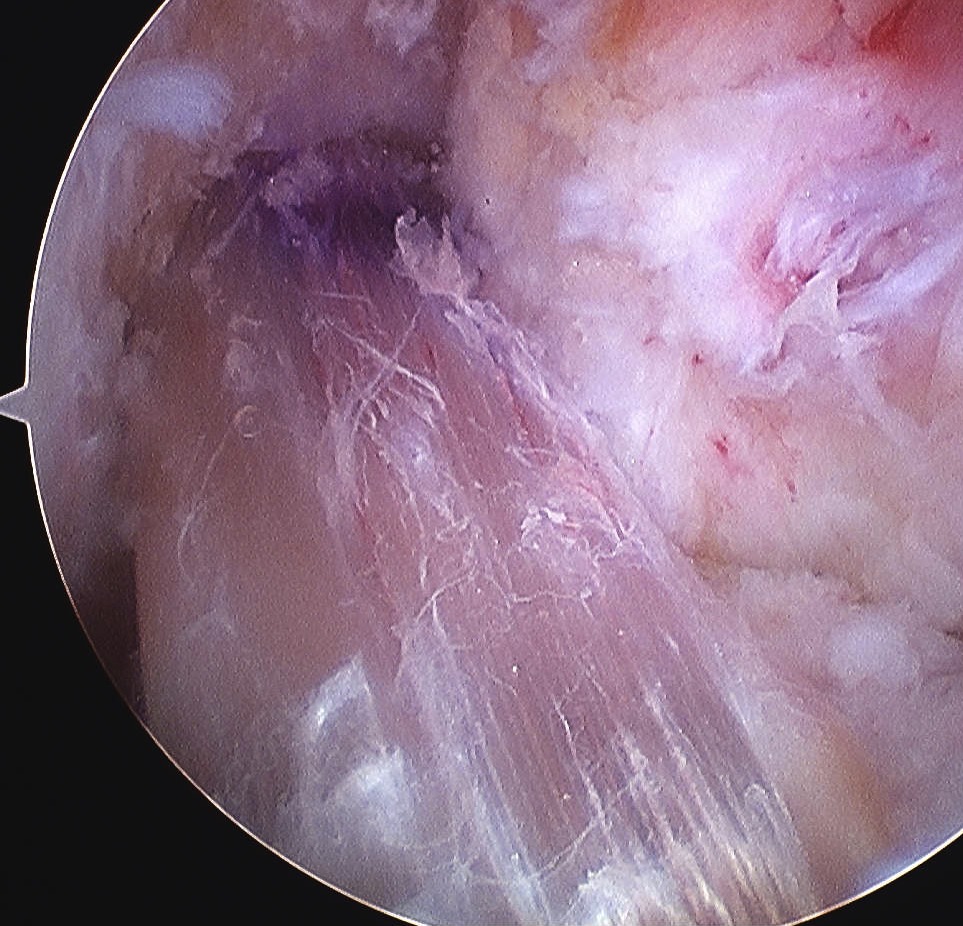

Pass Graft

Retrieve end of 1 nylon loop via tibial tunnel with grasper / probe

- place all 4 sutures of endobutton into loop and pull up through femoral tunnel

- separate sutures

- visualise femoral tunnel with camera

- use the pulling sutures to pull graft up into femoral tunnel

- helpful to wrap about artery forcep for traction

- then use both sutures to ensure that endobutton has flipped (rock each end back and forth)

- tension other end of graft and ensure cannot flip endobutton any further